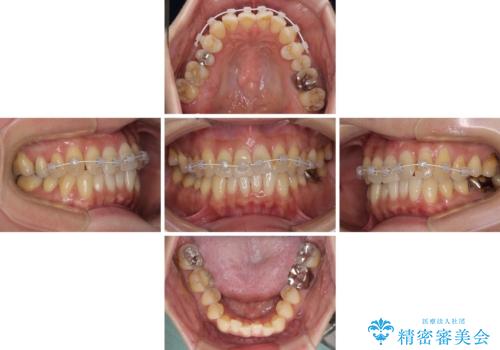

舌側転位している側切歯特有の、切縁の位置が不揃いであったり、根元が内側に引っ込んだ状態であったりという、インビザライン独特の仕上がりになることなく、きれいに整った歯列とすることができました。

- 1年7ヶ月

- 10-30回